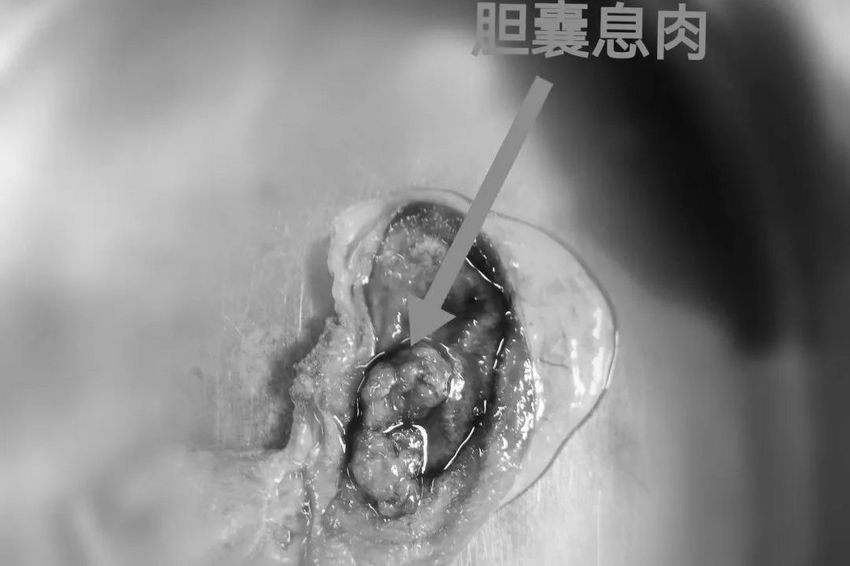

肝胆胰腺外科张永主治医师接诊后高度重视,立刻联系病理科预约术中快速冰冻,若为良性肿瘤,仅行单纯腹腔镜下胆囊切除术即可,若为恶性则需行腹腔镜胆囊癌根治术。令人庆幸的是,术中病理诊断是管状腺瘤,并未发生癌变,术后三天李先生便康复出院。

相比李先生,另一位50岁的马女士却没有这么幸运了。她因急性上腹痛在当地医院就诊,彩超结果提示为胆囊息肉、胆总管末端狭窄,并接受了手术治疗。

但术后不久,马女士再次出现腹痛,在郑州大学五附院肝胆胰腺外科就诊过程中,增强CT提示有胆囊恶性肿瘤可能,张永主治医师遂按肿瘤患者进行术前准备,术中联合崔卫东副主任医师、赵甦主治医师精细操作,胆囊肿瘤联合部分肝脏被完整切除,手术达到R0根治性切除并顺利完成。通过术后病理诊断,明确为胆囊神经内分泌癌。给予抗肿瘤综合治疗后,目前马女士的病情已有较明显恢复。